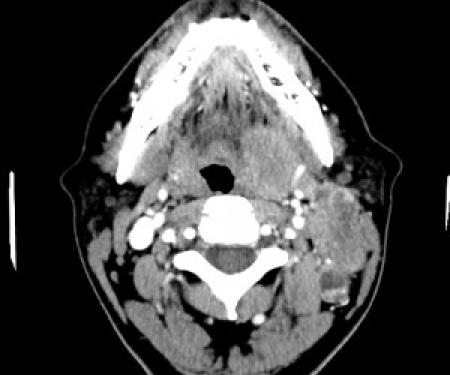

Diagnostic Imaging

Fox Chase Cancer Center is a recognized leader in medical imaging services. We offer a comprehensive range of radiology services using the latest technology to provide our patients with superior service for diagnostic imaging, staging, or determining the extent of the cancer, and cancer treatment planning. Our team of radiology experts offers digital mammography, MRI, CT scan or CAT scan, PET scan, digital X-ray, nuclear medicine and ultrasound.